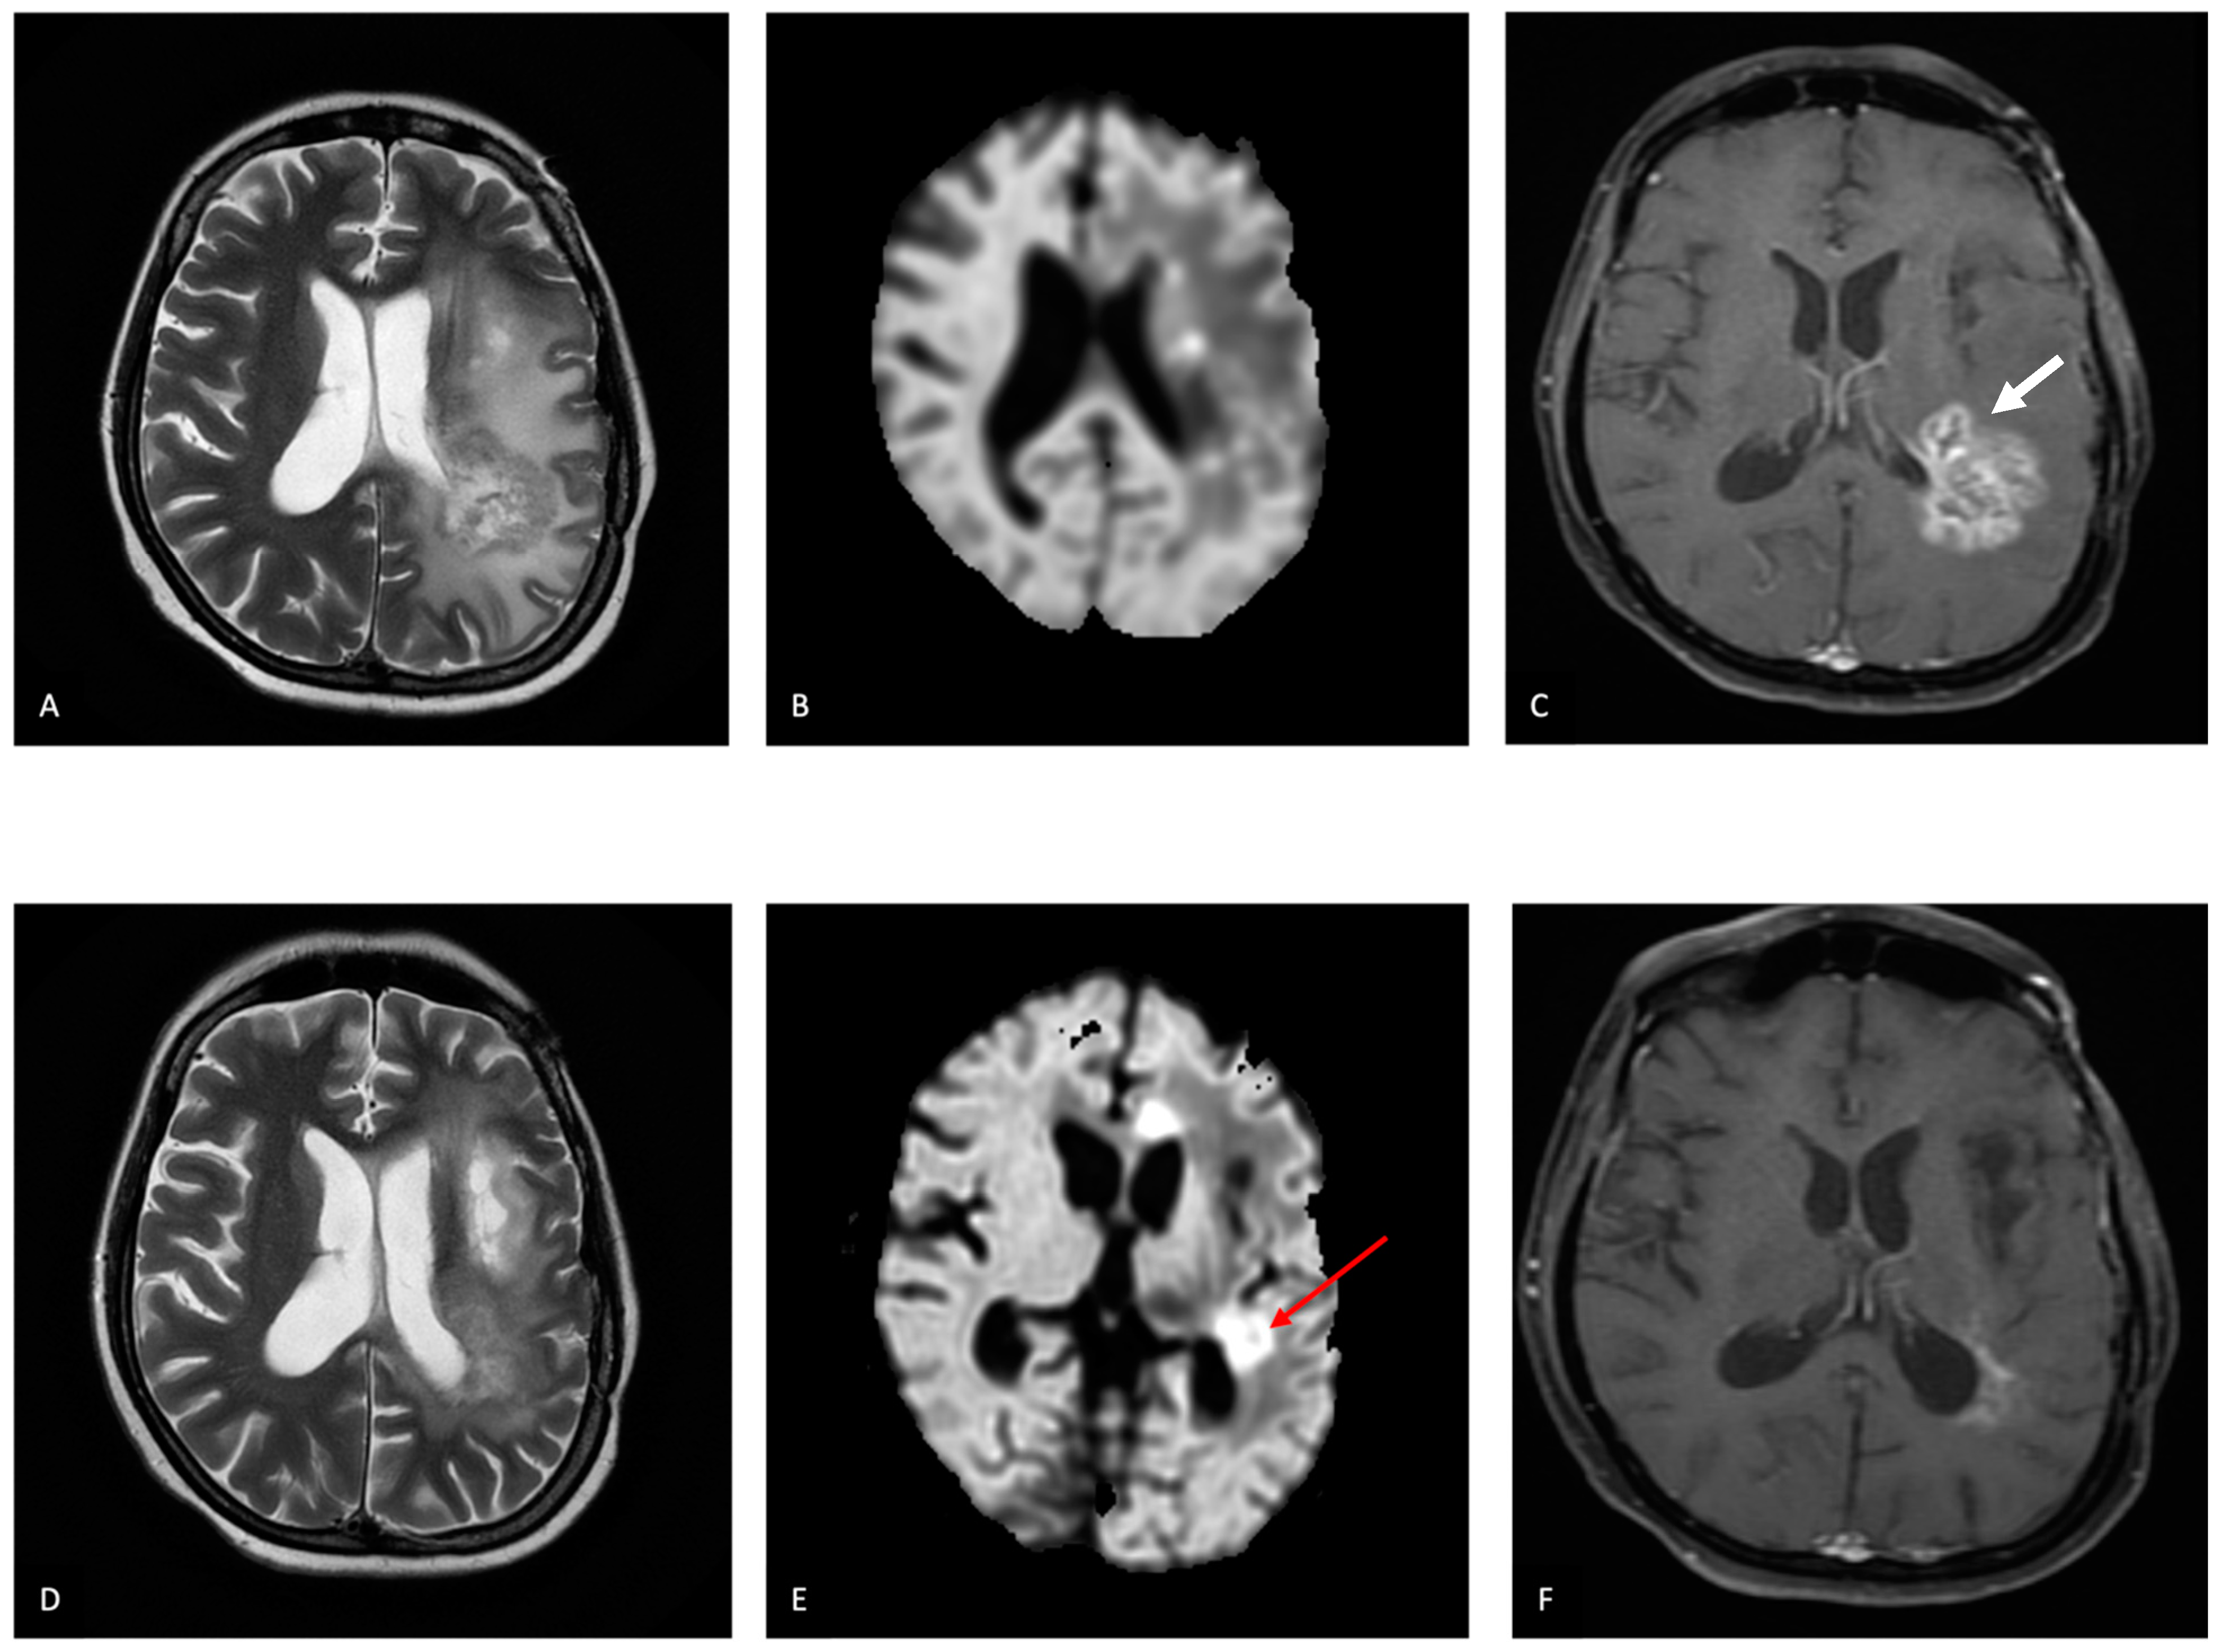

5.2. Diagnosis